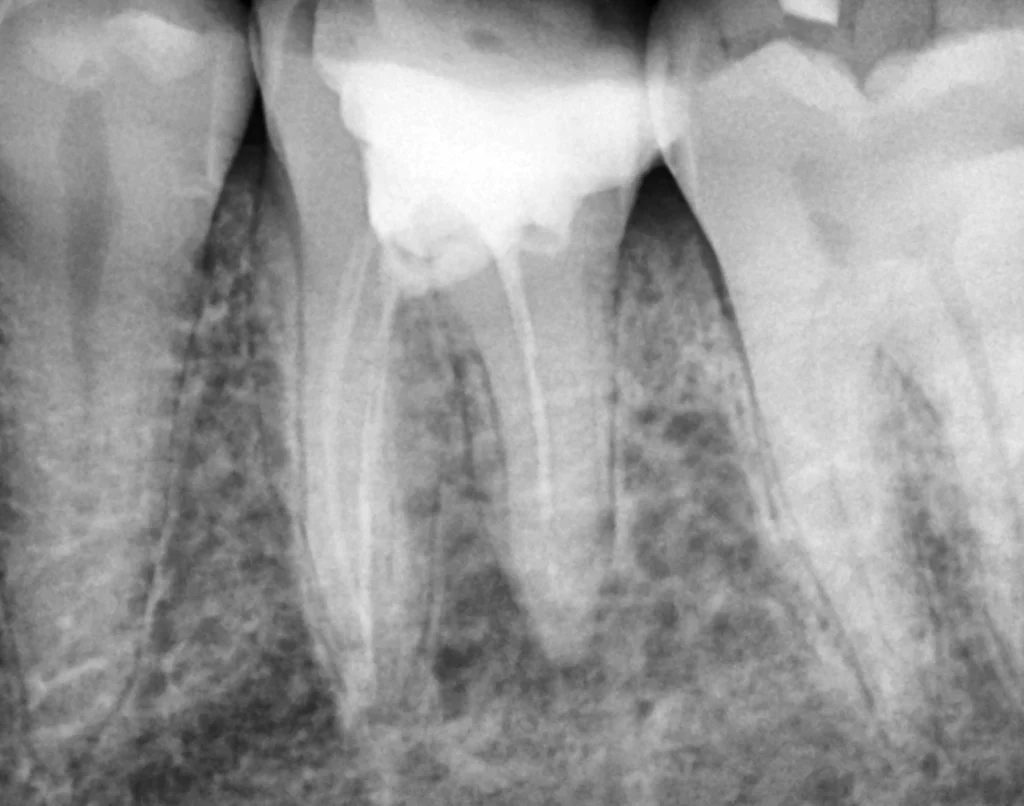

Root Canal Therapy in Beirut

Save your natural tooth and eliminate pain with advanced root canal treatment.

Root canal therapy is a highly effective procedure used to treat infected or damaged teeth.

At Smile Avenue, we use modern techniques to remove infection, relieve pain immediately, and preserve your tooth structure whenever possible. This treatment is often the best alternative to extraction and allows you to keep your natural smile for many years.